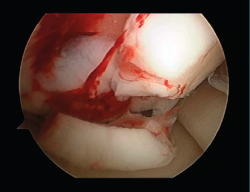

First surgery involves arthroscopy of the damaged joint. It assesses the chondral lesion to be treated and confirms whether it is amenable to the chondrocyte implantation technique (Figures 1 and 2). Other procedures are also carried out if needed, such as for example reconstruction of the anterior cruciate ligament, partial meniscectomies, meniscus implantation, patellar realignments, osteotomies, etc. Lastly, the cartilage sample is taken from a non-weight bearing zone (intercondylar zone or internal femoral condyle at its upper margin). The sample is extracted with biopsy forceps or, alternatively, using discectomy forceps. Between 3-4 rice grain-sized fragments of healthy cartilage are harvested (Figure 3). The biopsy material is placed in a sterile receptacle containing a culture medium (DMEN) (Figure 4). The material is kept at room temperature and is shipped to the laboratory as quickly as possible. A form should be completed (Figure 5), stating the joint, the location of the lesion and the size of the defect. Once in the laboratory, the sample is processed and cultured. After 4-6 weeks (depending on the case), the culture is ready for implantation.

Figure 1. Arthroscopic view of an Outerbridge grade IV acute chondral lesion of the internal femoral condyle.

Figure 2. Arthroscopic view of an Outerbridge grade IV chronic chondral lesion of the internal femoral condyle.